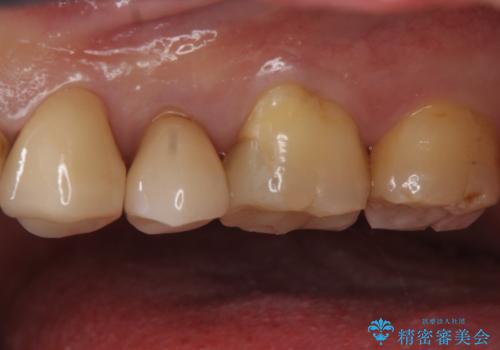

白い被せ物が入り希望に沿った処置となり

大変満足して頂けました。